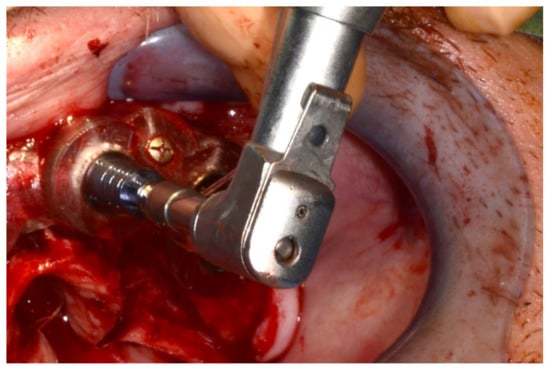

Figure 24.

Implant bed preparation using guided drills inserted into specific ad hoc drill handles.

Figure 25.

Guided implant insertion.